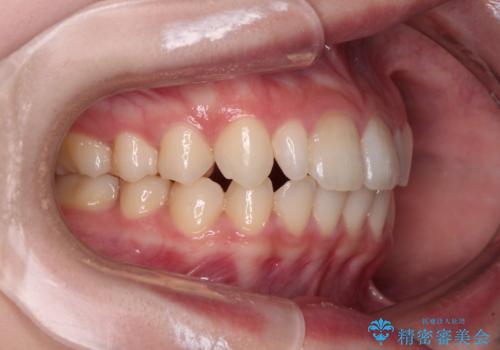

- 歯列のデコボコを気にして来院された患者様です。

安価に速やかに治療をしたいとのことで、メタルワイヤーにより矯正治療を行うこととしました。

上顎左右側切歯は矮小歯であり、矯正治療開始前にオールセラミッククラウンによる形態修正を兼ねた補綴治療を提案しましたが、特に気にならないとのことで、歯冠形態はそのままとしました。